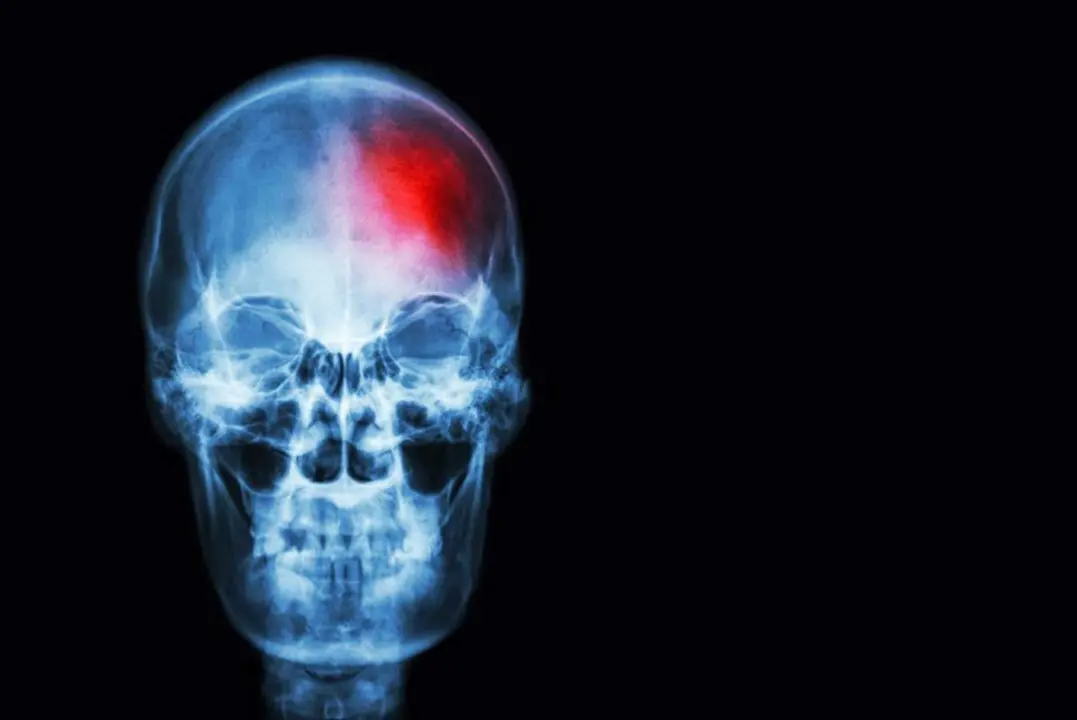

El coste de la atención a los ictus en Europa podría aumentar un 43% en 2040

Desde la Fundación Ictus, que impulsa el SAP-E, destacan que el ictus es una emergencia médica, y es que sólo en España cada año se producen 120.000 casos. La incidencia de esta enfermedad se ha duplicado en los últimos 30 años y las previsiones actuales señalan que continuará creciendo aún más. De hecho, se estima que para 2035 en Europa se producirá un aumento del 34 por ciento en el número de casos, superando los cuatro millones y medio.